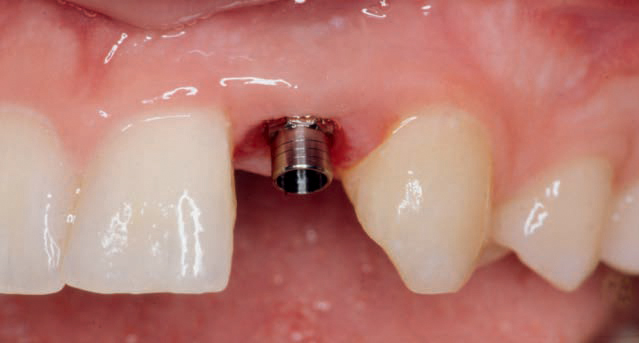

Implantatet, der skal være med til at erstatte den manglende tand, er sat på plads.

E: Under lokalbedøvelse blotlægges toppen af implantatet, og der skrues et lille forlængerstykke fast, som stikker ud gennem tandkødet (se illustration 3).

F: Tandlægen tager nu aftryk til den krone eller bro, som skal genskabe tandsættet. Kronen eller broen sættes fast på forlængerstykket, hvormed implantatbehandlingen er afsluttet (se illustration 4 og 5).